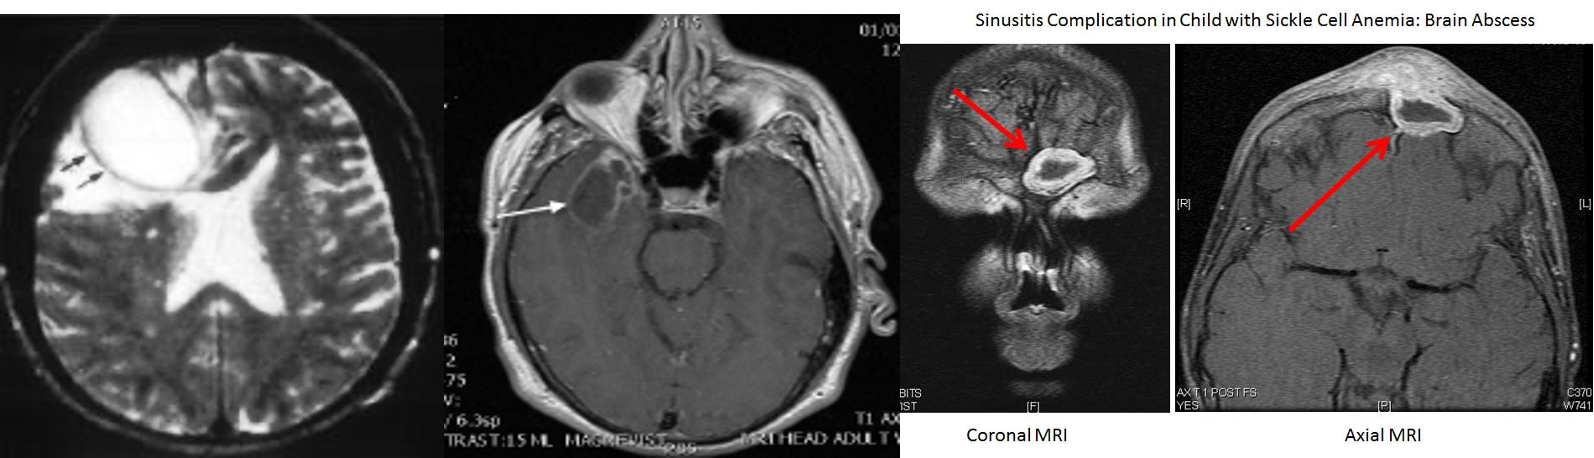

Central Nervous System

Suspected with:

- Very severe headache.

- Photophobia.

- Seizure.

- Other focal neurologic findings.

Complications

- Meningitis.

- Subdural empyema.

- Epidural abscess.

- Intracerebral abscess.

- Cavernous sinus thrombosis.

Clinicians should obtain a contrast-enhanced CT scan

of the paranasal sinuses and/or an MRI with contrast whenever a child is suspected of having orbital or CNS complications of ABS